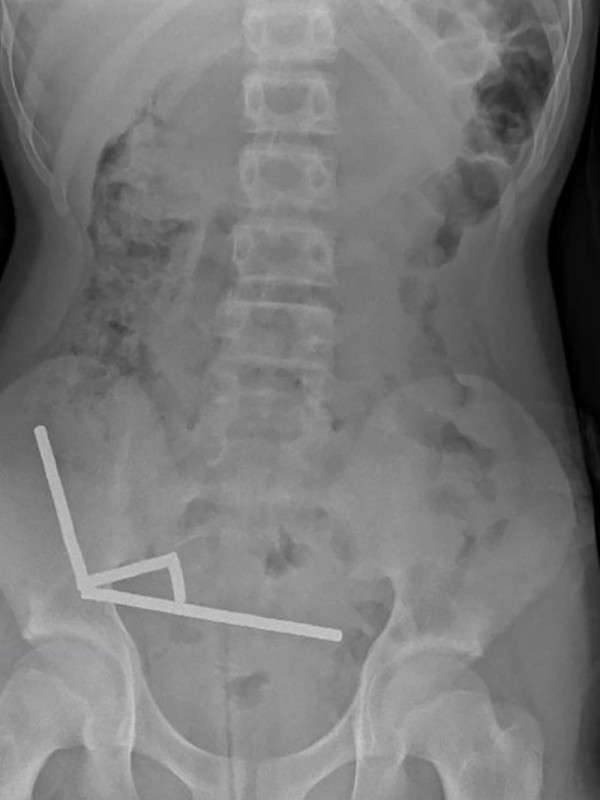

Мальчик четыре дня страдал от боли, прежде чем обратиться за медицинской помощью. Позже он признался, что около недели назад проглотил 80-100 неодимовых магнитов. Он рассказал врачам, что купил их в зарубежном интернет-магазине Temu. Рентген показал, что магниты, запрещённые в Новой Зеландии с 2013 года, образовали "четыре линейные цепочки" в кишечнике.Врачи, подготовившие отчёт, - Бинура Лекамалаге, Люсинда Дункан-Вере и Никола Дэвис - отметили: "В ходе операции были обнаружены несколько цепочек магнитов в тонком кишечнике и слепой кишке. Они соединились в правом нижнем квадранте, сдавив ткани и вызвав некроз".Длительное воздействие магнитов нарушило кровоток и снабжение тканей кислородом, что привело к их гибели.